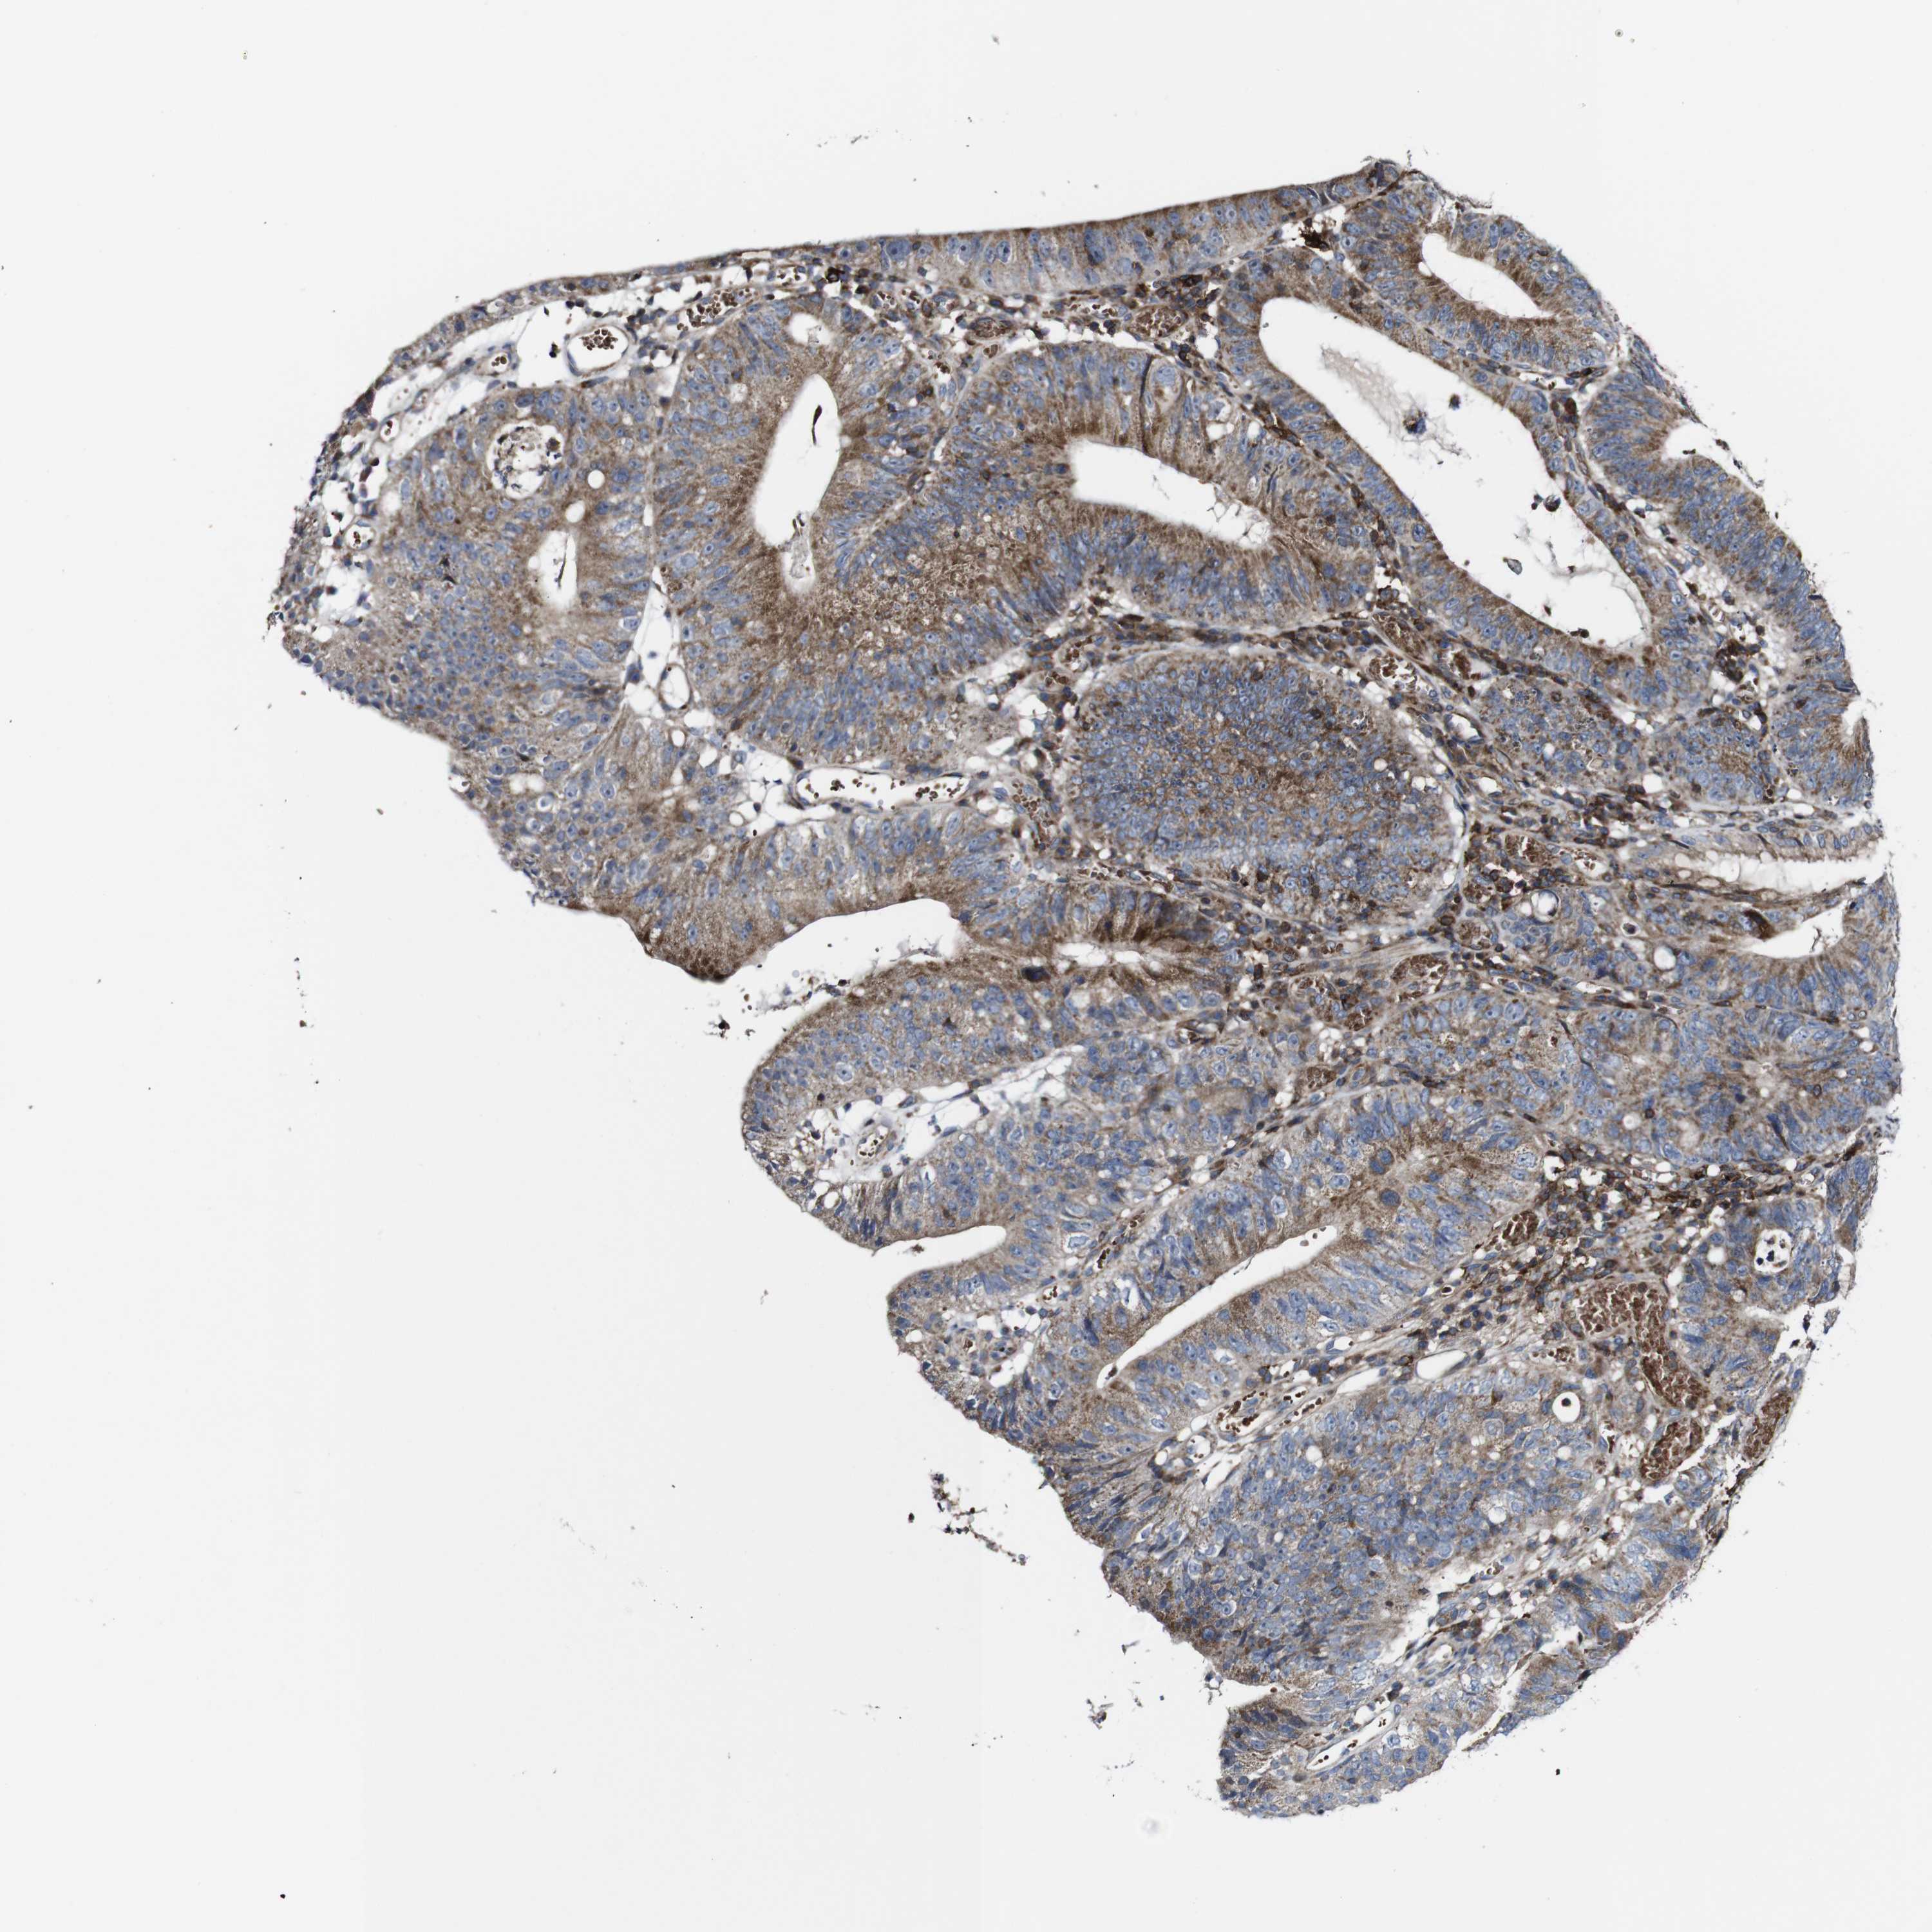

STOMACH CANCER - Protein expressioni

A mouse-over function shows sample information and annotation data. Click on an image to view it in a full screen mode. Samples can be filtered based on level of antibody staining by selecting one or several of the following categories: high, medium, low and not detected. The assay and annotation is described here.

Note that samples used for immunohistochemistry by the Human Protein Atlas do not correspond to samples in the TCGA dataset.

Antibody stainingi

Antibody staining in the annotated cell types in the current human tissue is reported as not detected, low, medium, or high, based on conventional immunohistochemistry profiling in selected tissues. This score is based on the combination of the staining intensity and fraction of stained cells.

Each image is clickable and will lead to virtual microscopy that enables deeper exploration of all samples and also displays staining intensity scores, fraction scores and subcellular localization as well as patient and tissue information for each sample.

Antibody HPA040820

Antibody CAB013089

Staining

High

Medium

Low

Not detected

Intensity

Strong

Moderate

Weak

Negative

Quantity

>75%

75%-25%

<25%

None

Location

Nuclear

Cytoplasmic/membranous

Cytoplasmic/membranous,nuclear

Adenocarcinoma, NOS